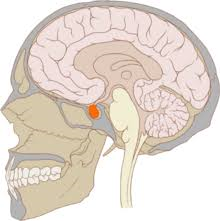

De plus, le sommeil est très important pour les jeunes car c'est pendant ce dernier qu'est sécrétée par le cerveau l'hormone de croissance, aussi appelée somatotropine. Celle-ci permet, quand on est jeune de grandir, et de régénérer les cellules quand on est adulte. Cette hormone est sécrétée au niveau de l'hypophyse, sous l'influence de deux autres hormones : le GHRH activateur (qui augmente la concentration intracellulaire de calcium des cellules qui sécrètent l'hormone de croissance) et la somatostatine inhibitrice (qui a un contrôle inhibiteur sur la sécrétion de la somatotropine). L'hormone de croissance agit indirectement sur les cartilages. Elle est transportée jusqu'aux cellules du foie où elle se fixe sur des récepteurs spécifiques. Cela provoque la synthèse et la libération d'un facteur qui stimule la maturation et la croissance de l'os.

Ainsi, les jeunes doivent impérativement avoir un bon sommeil car la sécrétion de la somatotropine est maximale à l'adolescence. Sans cette molécule, ils pourraient avoir une petite taille toute leur vie !